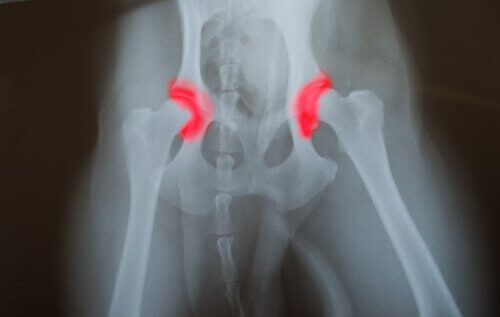

동물 병원을 찾는 동물들의 25%가 정형 외과적 질환과 골관절염으로 인한 것이다. 이런 경우 중 최소 25%가 칼슘 및 다른 필수 영양소가 부족한 불균형한 식습관으로 인한 것이다.

하지만 새끼 강아지에게 너무 많은 사료를 주는 경우, 체중이 늘고 권장 속도보다 성장이 더 빠를 수 있다. 이것은 뼈에 너무 많은 압박을 주고 다음과 같은 질병을 유발할 수 있다.

- 뼈연골증

- 고관절 이형성

- 근육 돌기 파열 및 균열

1974년, 단백질, 인, 칼로리가 높은 식습관을 가진 12쌍의 그레이트 데인에 대한 연구가 이루어졌다. 그리고 연구 결과, 앞서 언급한 질병들이 이러한 식습관을 가진 개들에게 좀 더 빈번하게 발생하는 것으로 나타났다.

불균형한 식사를 하는 대형견과 비교해서, 균형 잡힌 식사를 하는 대형견들은 과잉 성장 관련 질병을 덜 겪는 것으로 드러났다. 고관절 이형성증 또한 대형견, 너무 많이 먹는 개에게 가장 흔히 발생하는 질병 중 하나였다.

성견의 경우, 과도한 식사는 심각한 질병을 유발하는 것으로 드러났다. 나이든 개의 경우, 관절의 악화가 가장 흔한 증상 중 하나였다.